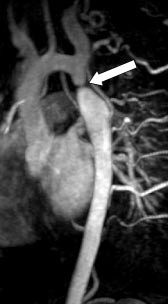

Ved medfødte aortabueanomalier inkludert coarctatio aortae vil MR med MRA kunne gi all nødvendig informasjon og erstatte kateterangiografi. Ikke minst ved mistanke om koarktasjon burde MR være førstevalg. MRA gir en fullgod anatomisk oversikt over hele torakalaorta (fig 6), og måling av blodstrømshastighet i det stenotiske området kan brukes til å beregne trykkgradienten over stenosen.

Kontrastforsterket MRA representerer et betydelig fremskritt for MR-diagnostikken av intraabdominal karanatomi. Metoden har potensial til å overta mye av kateterangiografiens diagnostiske rolle i dette kargebetet. I diagnostikk av signifikant nyrearteriestenose har metoden sensitivitet og spesifisitet på godt over 90 % ved sammenlikning med kateterangiografi (16 – 18). MRA vil kunne utelukke signifikant stenose i de største nyrearteriene, men metoden gir fortsatt for dårlig fremstilling av de intrarenale grener. Ved hypertensjon hos yngre personer der man kan mistenke fibromuskulær dysplasi, bør det derfor fortsatt gjøres kateterangiografi. Kontrastforsterket MRA har ikke minst vist seg nyttig hos nyre- og levertransplanterte pasienter (19). Ved mistanke om arteriestenose vil metoden kunne selektere de pasienter som bør utredes videre med kateterangiografi før ev. ballongdilatasjon av stenosen (fig 8). Ved å gjøre flere MRA-opptak etter samme kontrastmiddelbolus kan både arteriefase og venefase fremstilles separat, noe som er særlig nyttig ved utredning av levertransplantater (fig 9). Den gode fremstillingen av sentrale arterier og vener gjør metoden også egnet ved vurdering av tumoroperabilitet i lever og pancreas.